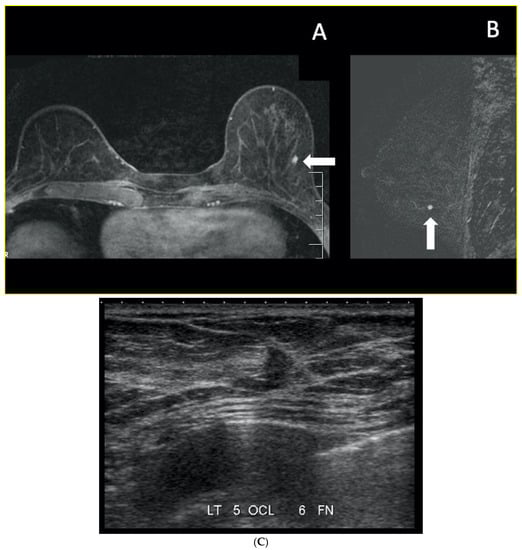

5. Ultrasound (US)